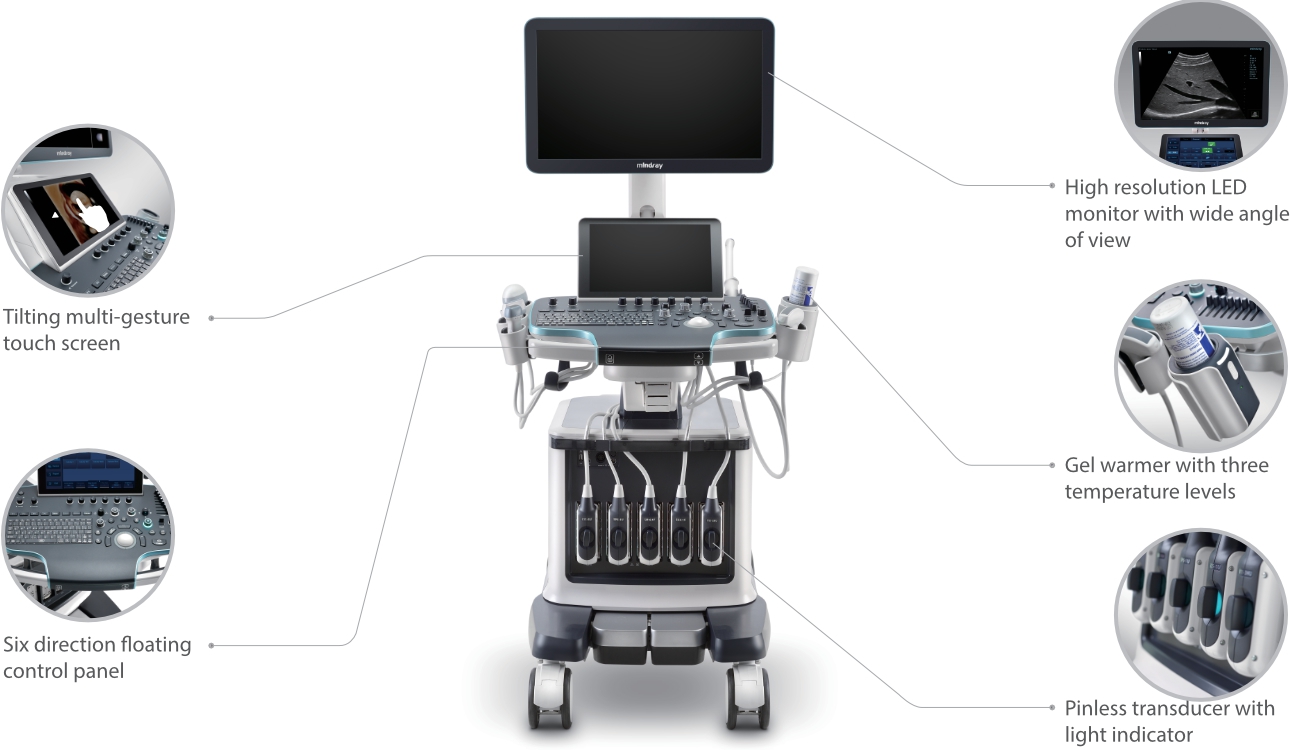

Resona 7

Gelombang Baru dalam Inovasi Ultrasound

Sejak didirikan, Mindray terus mencari cara baru untuk meningkatkan keandalan diagnostik. Didukung Teknologi ZONE Sonography? terkini, platform ZST+ baru Resona 7 meningkatkan kualitas gambar ultrasound melalui pengambilan zona dan pemrosesan data saluran.

Selain kualitas gambar premium, Resona 7 juga meningkatkan kemampuan penelitian klinis dengan V Flow revolusioner untuk evaluasi hemodinamika vaskular, serta pengambilan penampang tercanggih dari rangkaian data 3D untuk diagnosis CNS pada janin. Kombinasi pengoperasian multisentuh berbasis gerakan yang paling intuitif dengan semua fitur klinis penting membuat Resona 7 menjadi gebrakan baru dalam inovasi ultrasound.